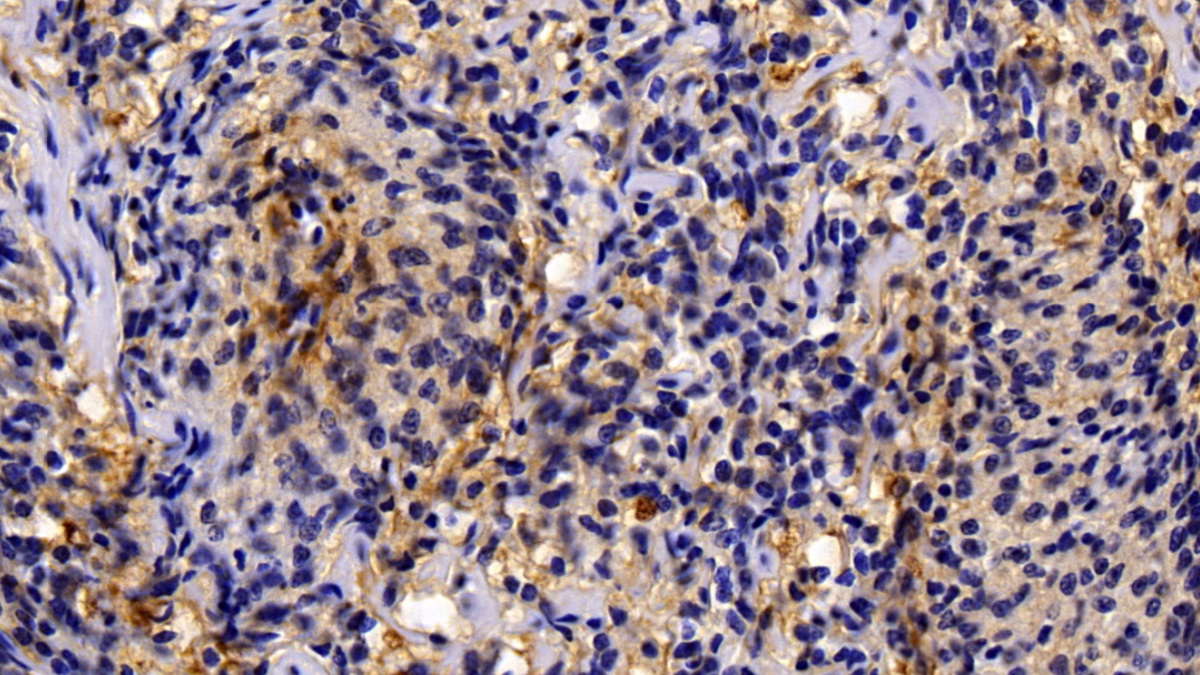

Использование высококачественных первичных антител является неотъемлемым условием получения точных и воспроизводимых результатов в современных научных исследованиях. Например, в рамках онкологического исследования удалось достоверно идентифицировать экспрессию белка PD-L1, что сыграло ключевую роль в оценке потенциальной эффективности иммунотерапии. Применение надежных антител обеспечило стабильность сигнала и высокую специфичность детекции, что позволило получить данные, пригодные для публикации в рецензируемых научных изданиях.

Способы применения первичных антител

Первичные антитела используют в разных методах: от вестерн-блоттинга до иммунофлюоресценции и проточной цитометрии. Всё решает подготовка: нужно грамотно выбрать буфер, точно рассчитать, сколько продукта добавить, и не затянуть с инкубацией. Например, в вестерн-блоттинге без правильной блокировки мембраны фон может всё испортить, а в иммунофлюоресценции фиксация клеток решает, будет ли сигнал ярким. Мы не просто продаём реагенты, а помогаем довести эксперимент до результата: подбираем реагенты и даём советы по методам, если есть специфика в протоколах производителя. Нужен особый подход? Оформите спецзаказ по ссылке — мы найдём решение для вашего проекта.